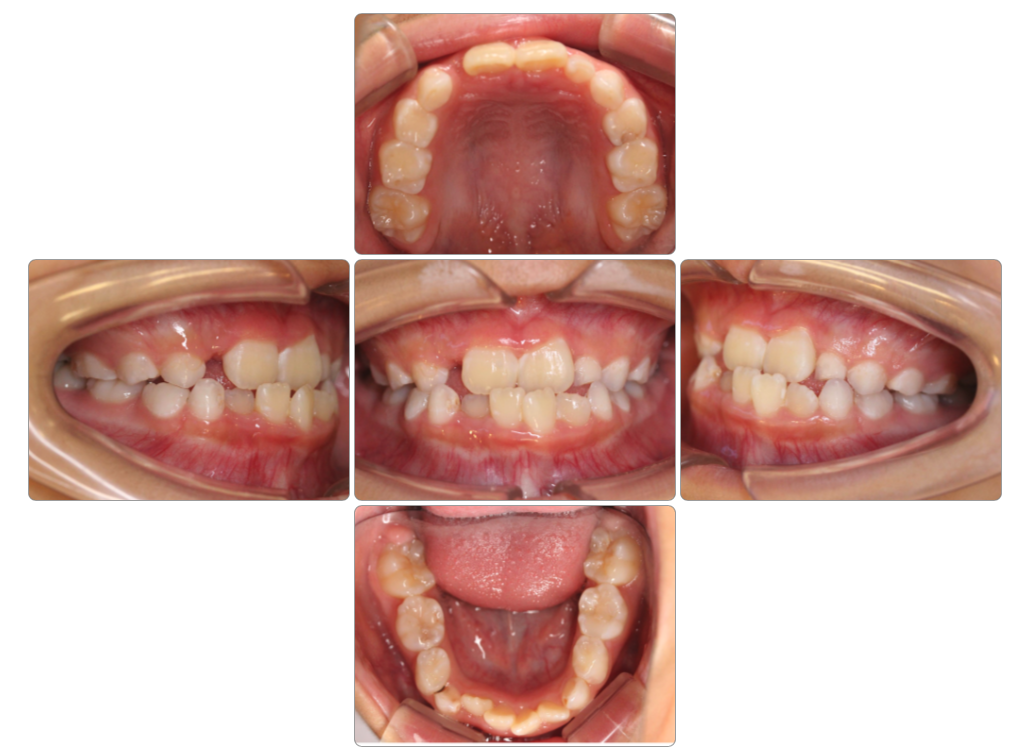

Before

after

| 初診時 | 8歳0ヵ月 |

| 治療期間 | 1年半 |

| 費用 | ¥550,000・調整料 ¥5,500/月 |

| 使用装置 | マイオブレイス・BBI・BWS |

| リスクと副作用 | |

| 原因と考察 | 顎の上がった姿勢になっており舌が前歯の裏側にまで届いていません。ここに丸飲み習慣が重なり前歯が後ろに倒されています。体幹指導と共に丸飲みにならないための食生活指導が必要です。 |